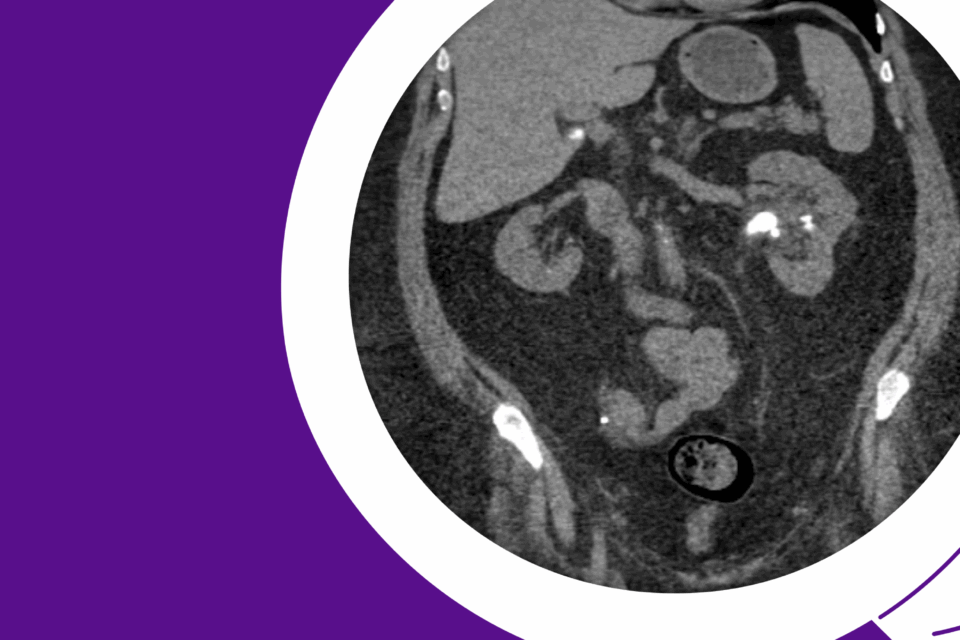

Robotic Management of Giant Hydronephrosis & Contralateral UPJ Obstruction

Dr. Brian W. Chao details his approach to robotic nephrectomy and pyeloplasty for incidentally discovered giant hydronephrosis and contralateral UPJ obstruction.